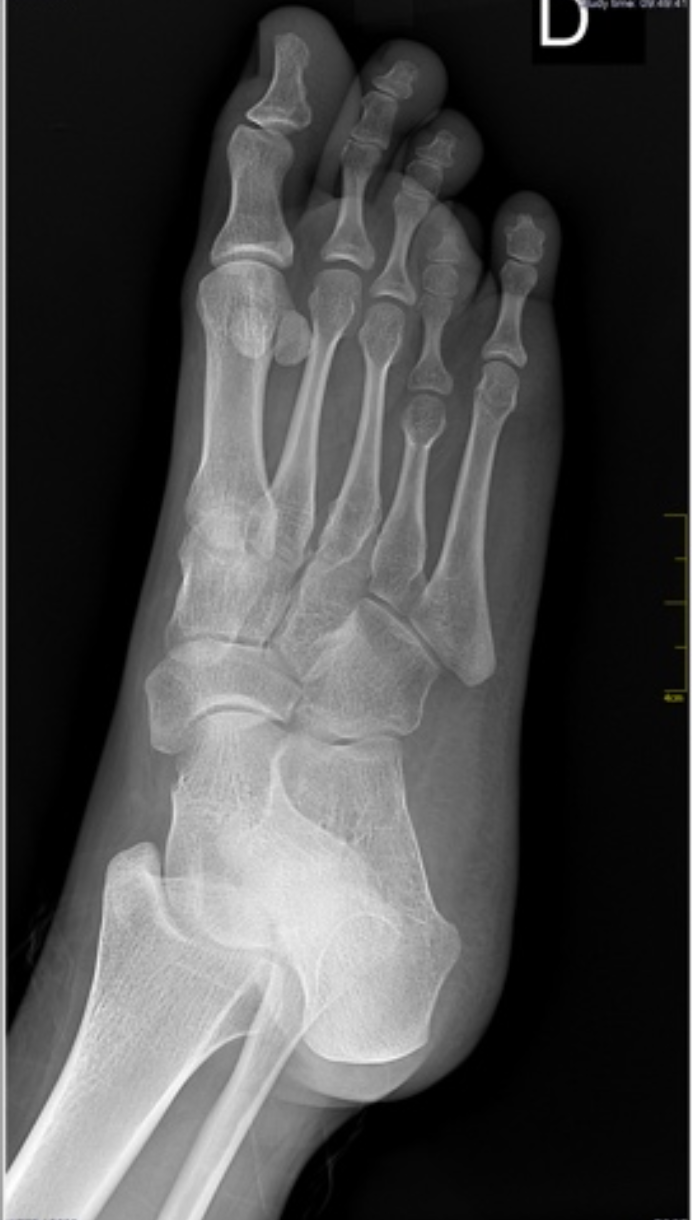

Braquimetatarsia e displasias dos pés

A braquimetatarsia provoca encurtamento metatarsal, sobrecarga e desconforto estético/funcional. O manejo pode ser conservador com palmilhas e calçados adequados, porém casos sintomáticos indicam alongamento metatarsal. Técnicas incluem osteotomia com enxerto intercalar e fixação, ou alongamento gradual por mini-fixador externo, permitindo ganhos controlados e adaptação de partes moles. Em displasias associadas, avalia-se alinhamento do retropé/antepé e corrige-se deformidades concomitantes. O planejamento cuidadoso de comprimento e arco plantar visa distribuir cargas, aliviar dor e melhorar o uso de calçados e a estética, com reabilitação e retorno progressivo.